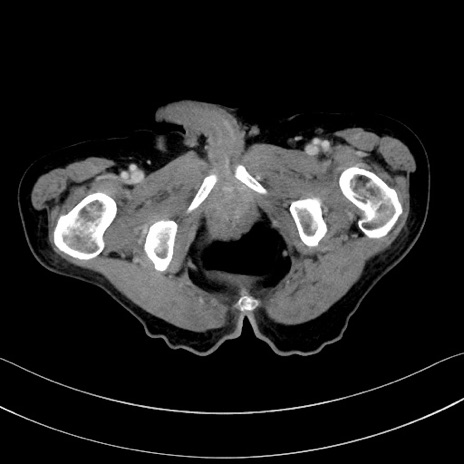

症例28(横断像)

【症例】60歳代男性

【主訴】嘔吐

【現病歴】胃癌にて胃全摘後。食思不振が悪化し、夜中に嘔吐することがある。

【既往歴】胃癌、胃全摘、脾摘、胆摘後

【データ】WBC 5900、CRP 10.56